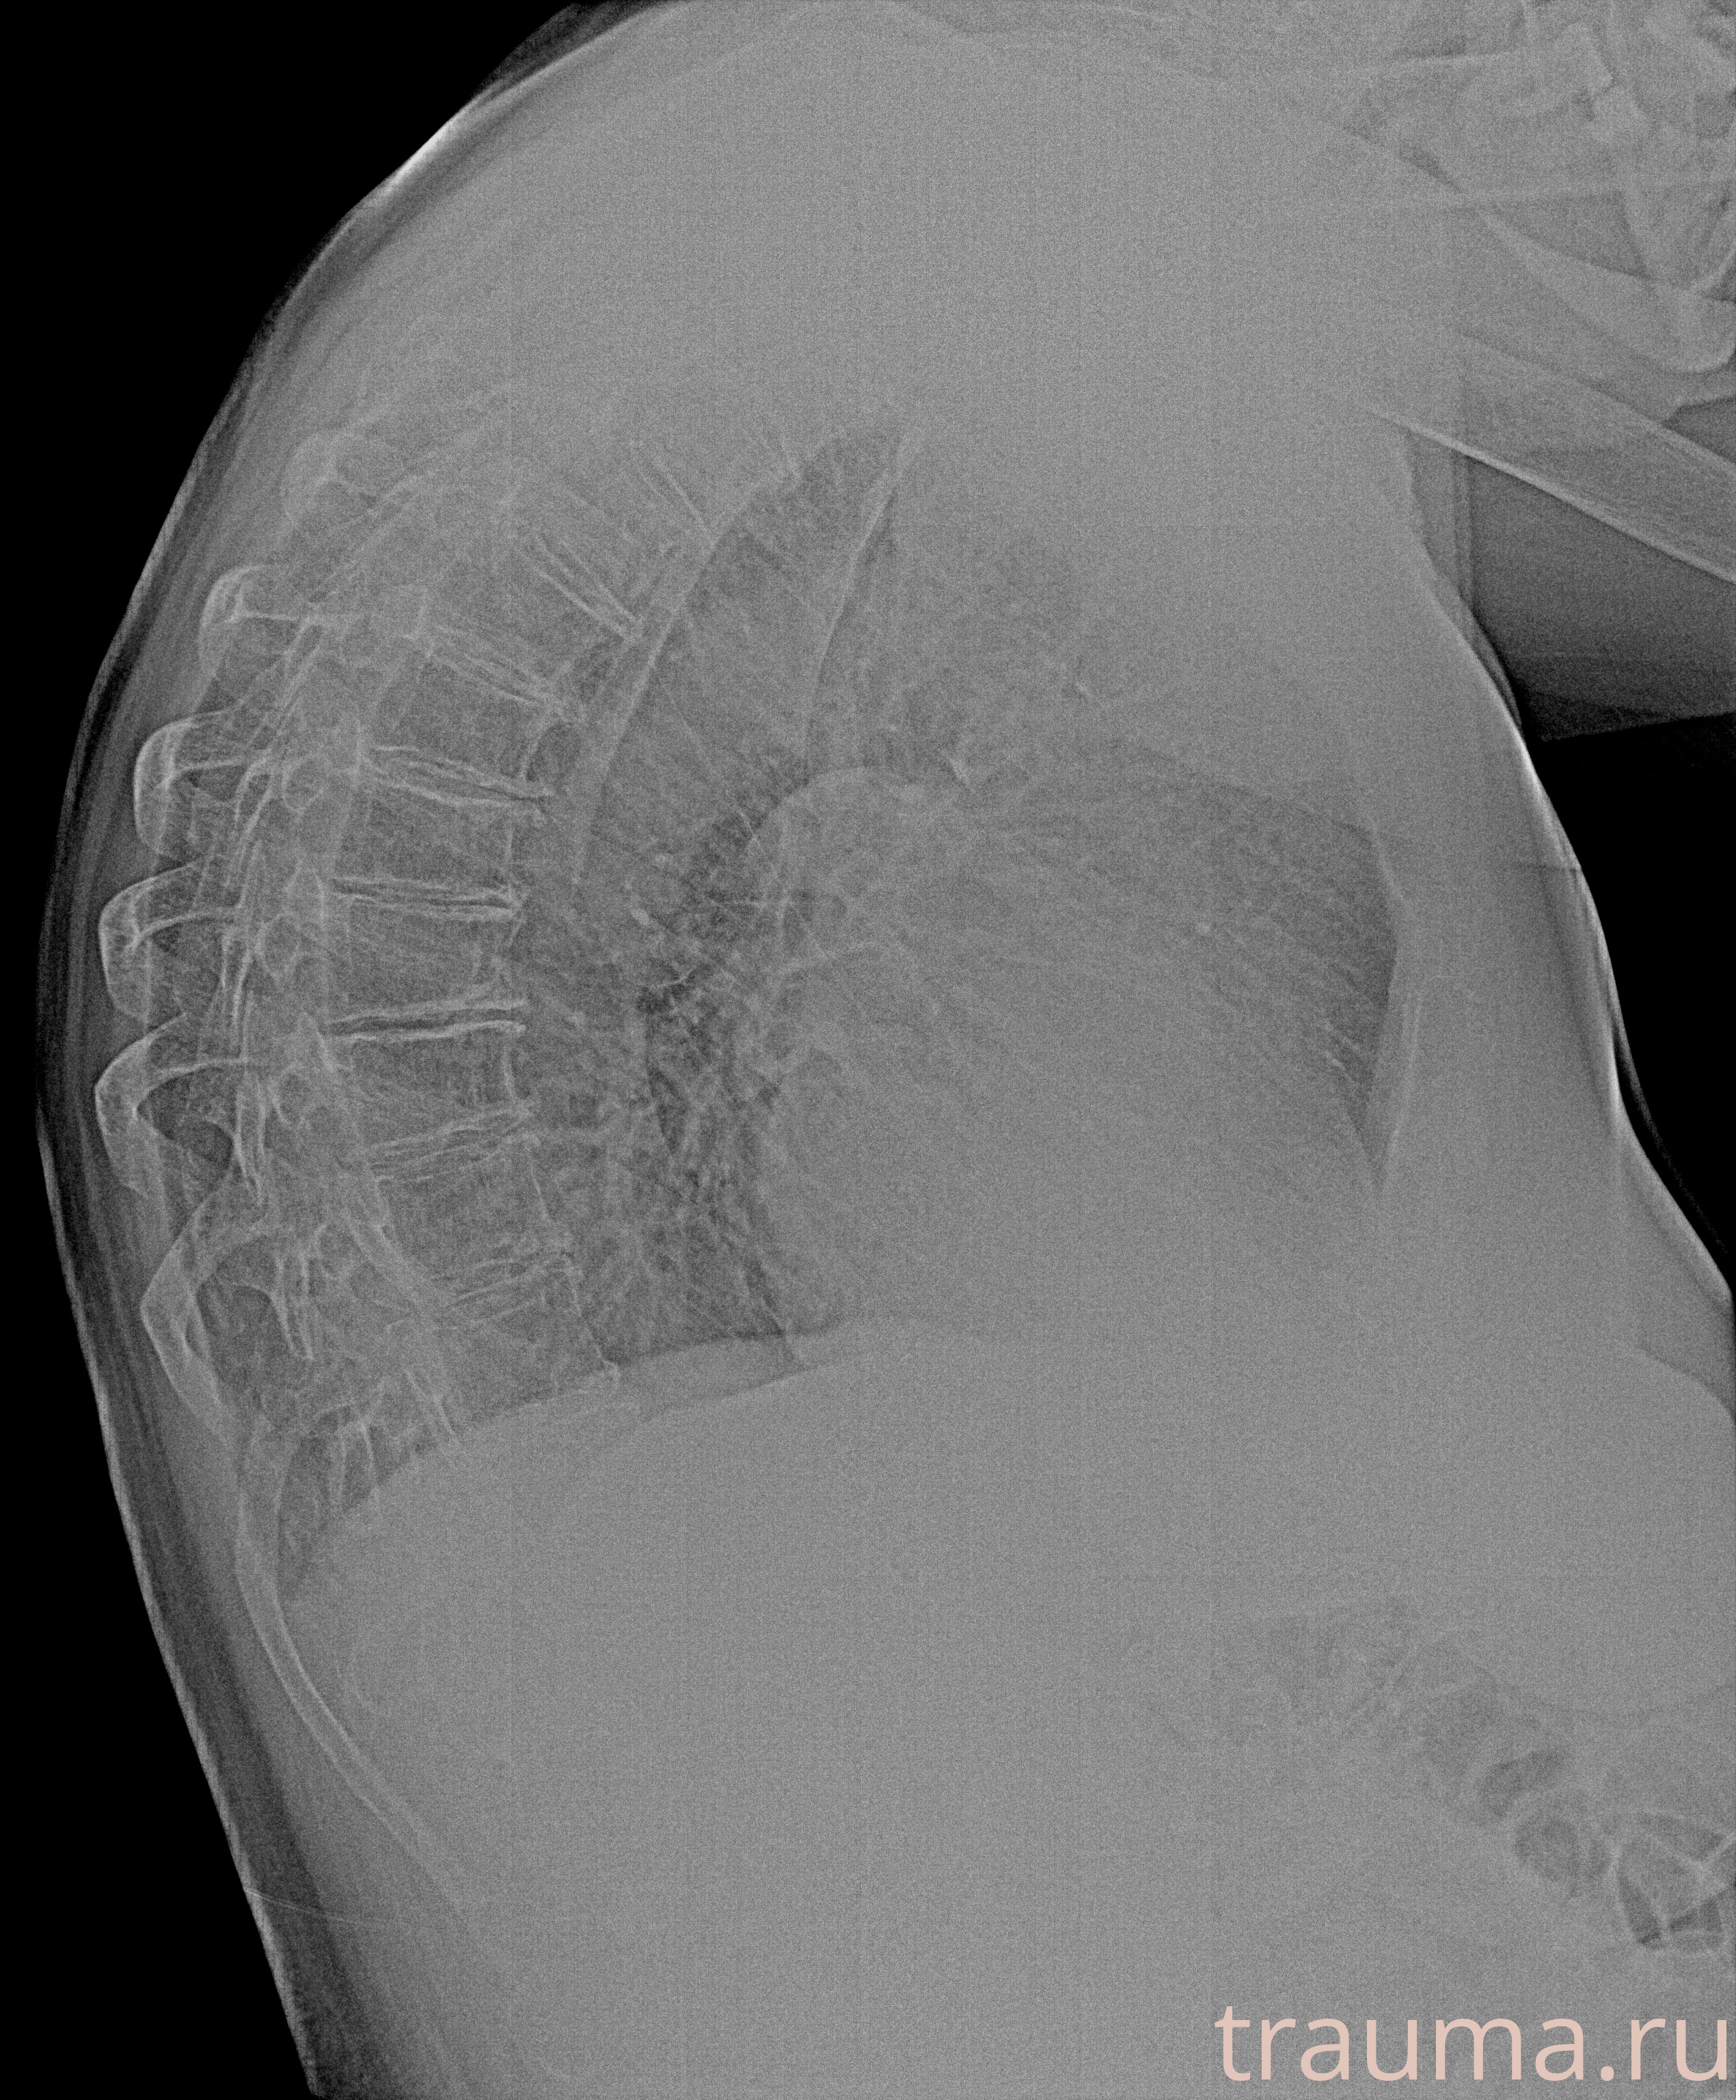

Рентгенограммы

Рентген на дому: по вашему адресу приезжает врач-рентгенолог, травматолог-ортопед с мобильным рентгеновским аппаратом, проводит диагностику травмы или заболевания, делает необходимые рентгенограммы, дает рекомендации по дальнейшему лечению. Получить качественные снимки в домашних условиях возможно благодаря уникальной методике, разработанной МосРентген Центром для института  Склифосовского

при переломе шейки бедра и пневмонии от компании МосРентген Центр - партнера Института имени Склифосовского